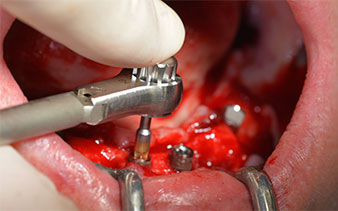

Questa è la prossima posizione programmata nel sistema Implantmed. Qui è possibile vedere il contrangolo W&H impugnato a un angolo di 45 gradi in posizione medio-caudale, nella zona del 45, al fine di salvaguardare il nervo mentoniero. Il forame mentoniero è un punto di riferimento anatomico per tutte le perforazioni in quest'area. I fori successivi sono realizzati con una velocità ridotta, pari a 300 giri/min (Fig. 10 e 11).

Il prossimo passaggio programmato prevede ancora il posizionamento degli impianti. Solitamente, in questa fase il nostro studio utilizza una coppia di 32 Ncm (Fig. 12 e 13).

L'alta solidità è un requisito indispensabile per una ricostruzione immediata. Per garantirla, in questo caso il foro non è stato filettato. L'unità di perforazione Implantmed di W&H è dotata di una modalità speciale per questo scopo, che può essere selezionata direttamente ed è indispensabile in molte situazioni. In fase di posizionamento degli impianti, i giri finali hanno superato il valore di 32 Ncm e sono stati terminati a mano. In questi casi, consigliamo l'utilizzo della funzione autofilettante del sistema di implantologia e la rotazione degli impianti all'indietro e in avanti, per diverse volte. Questo permette all'impianto di assumere gradualmente la posizione finale, evitando un'eccessiva pressione all'osso (Fig. 14).